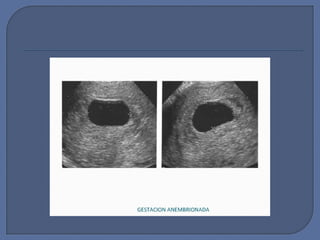

 Instrumento diagnóstico ideal.

 Cuando se aplica apropiadamente,

puede usualmente hacer un diagnóstico

rápido y definitivo.

 La ecografía de rutina al inicio del

embarazo hace que se efectúe una mejor

valoración de la edad gestacional.

 Cuando es visible por 1ª vez, el saco

gestacional parece estar vacío y puede

ser semejante al “saco

pseudogestacional”.

 Algunas características precoces del

saco gestacional normal son:

• Forma redonda

• Localizados en el fondo uterino

• Un anillo ecogénico rodea al saco